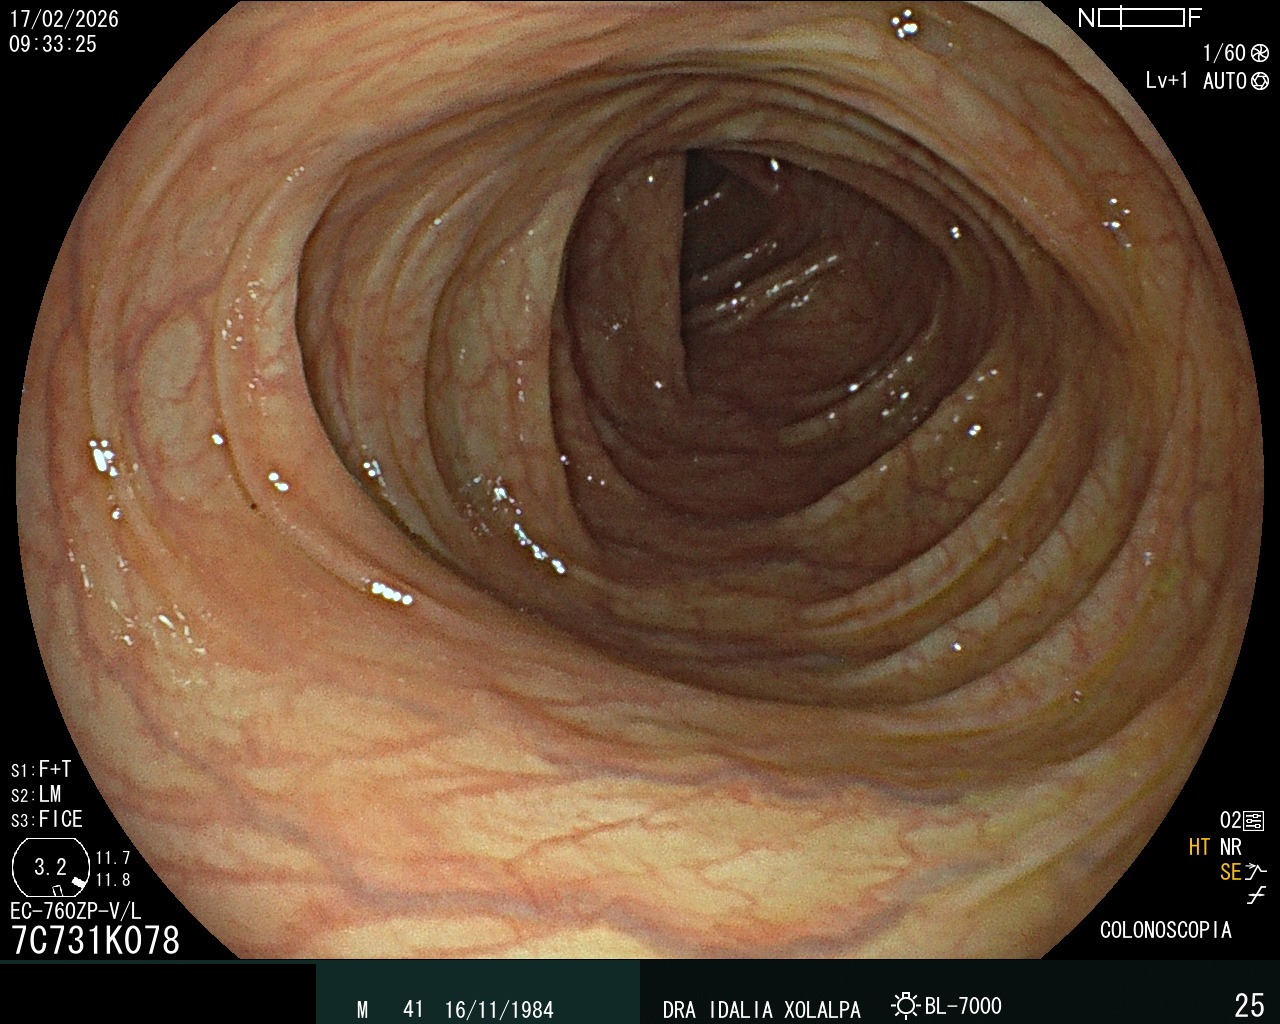

Colon Normal